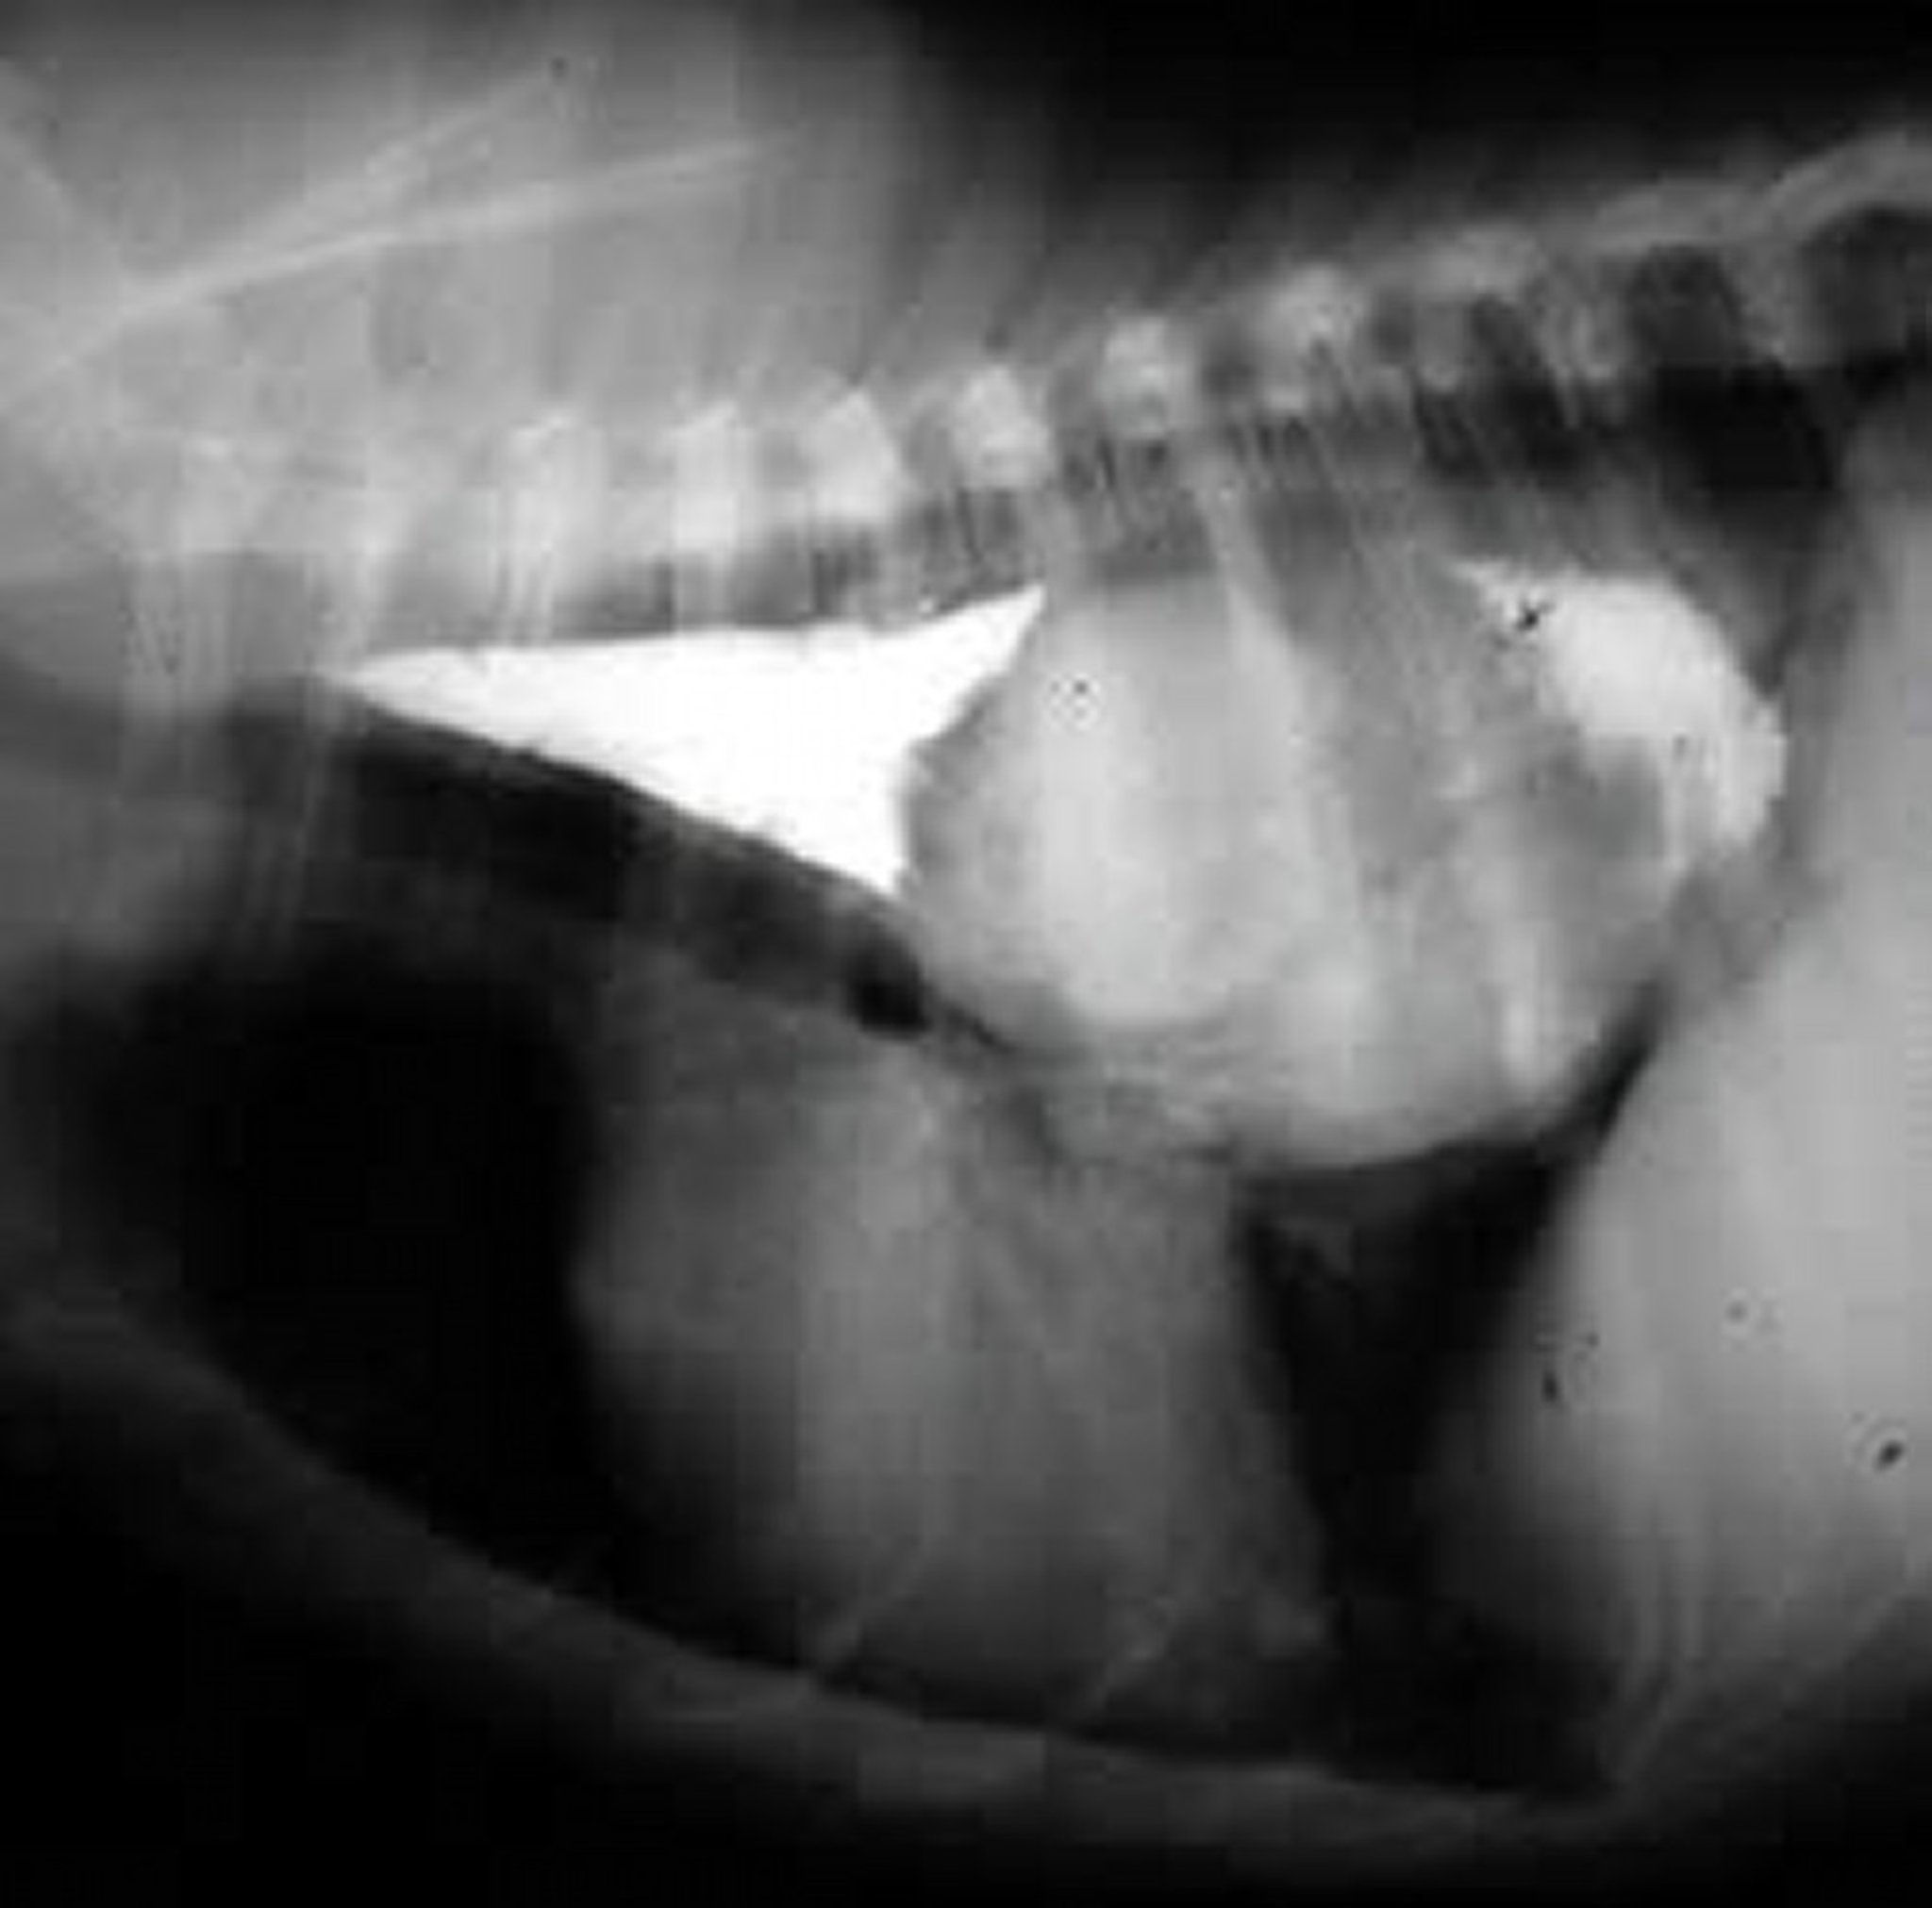

Spirocerca lupi, esôfago, cão

S lupi infection in a dog. Lateral thoracic radiograph obtained after oral administration of a positive contrast agent. In the caudal esophagus, there is a large soft-tissue opaque mass that is ventrally displacing the heart. The mass is outlined cranially and caudally by positive contrast.

Courtesy of Dr. Ronald Green.